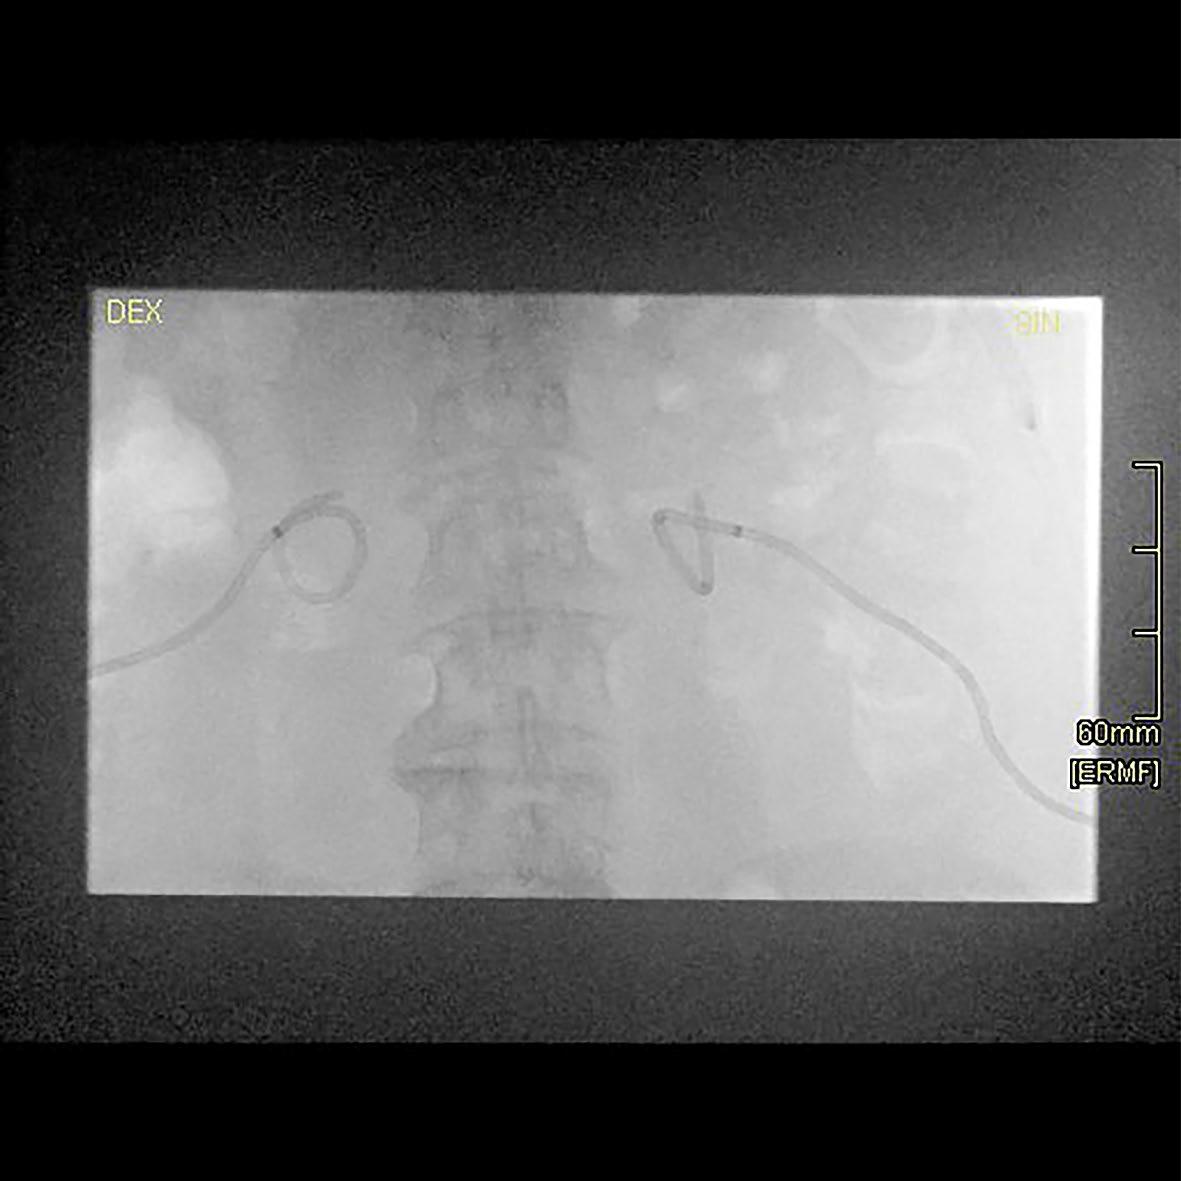

Fluoroscopic image of the same patient. Catheter position is correct, despite non-fixing suture on the right side.